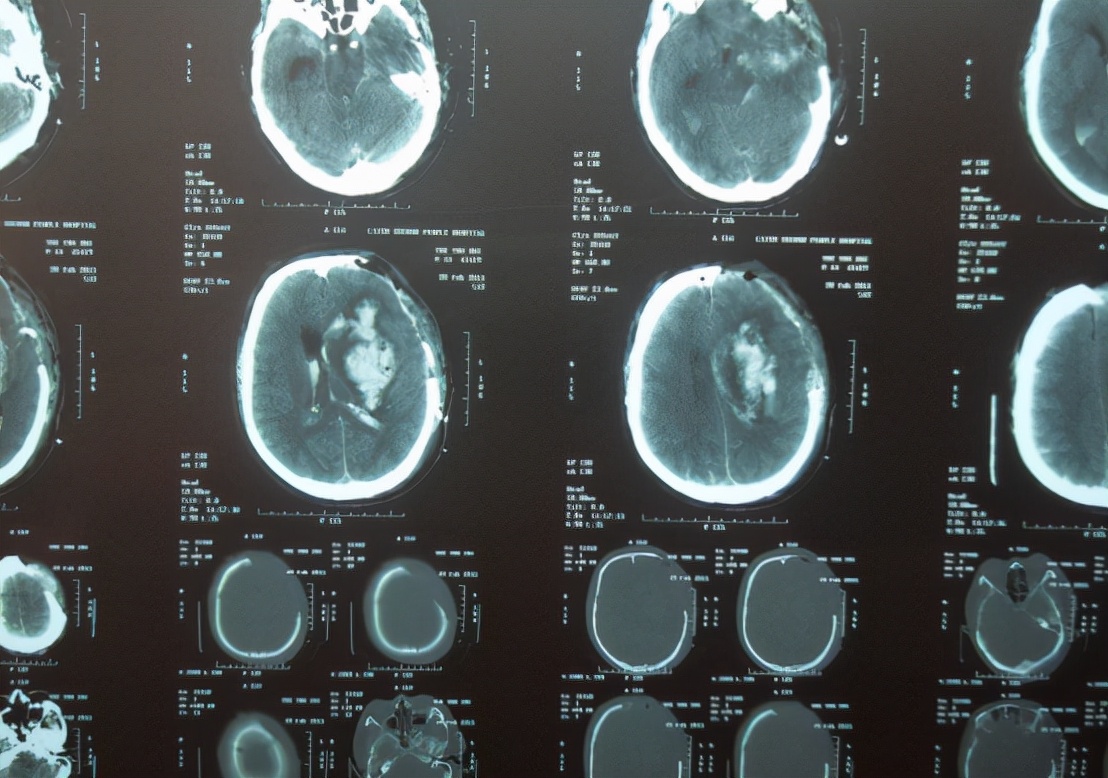

医学上很难从外观上判断出患者是否患有脑出血 ,而是要通过严谨医学手段来检查。因此,患者必须要去医院做脑部CT才能最终确诊。但是平时可以通过一些早期症状来预测是否患有脑出血。

作为早期诊断脑出血的唯一治疗手段,它的准确性非常高。检查颅脑时, 颅内出现高密度影像时,就可以判断此人患上脑出血; 极少数个别情况的患者由于脑出血的面积很小,不易被察觉。